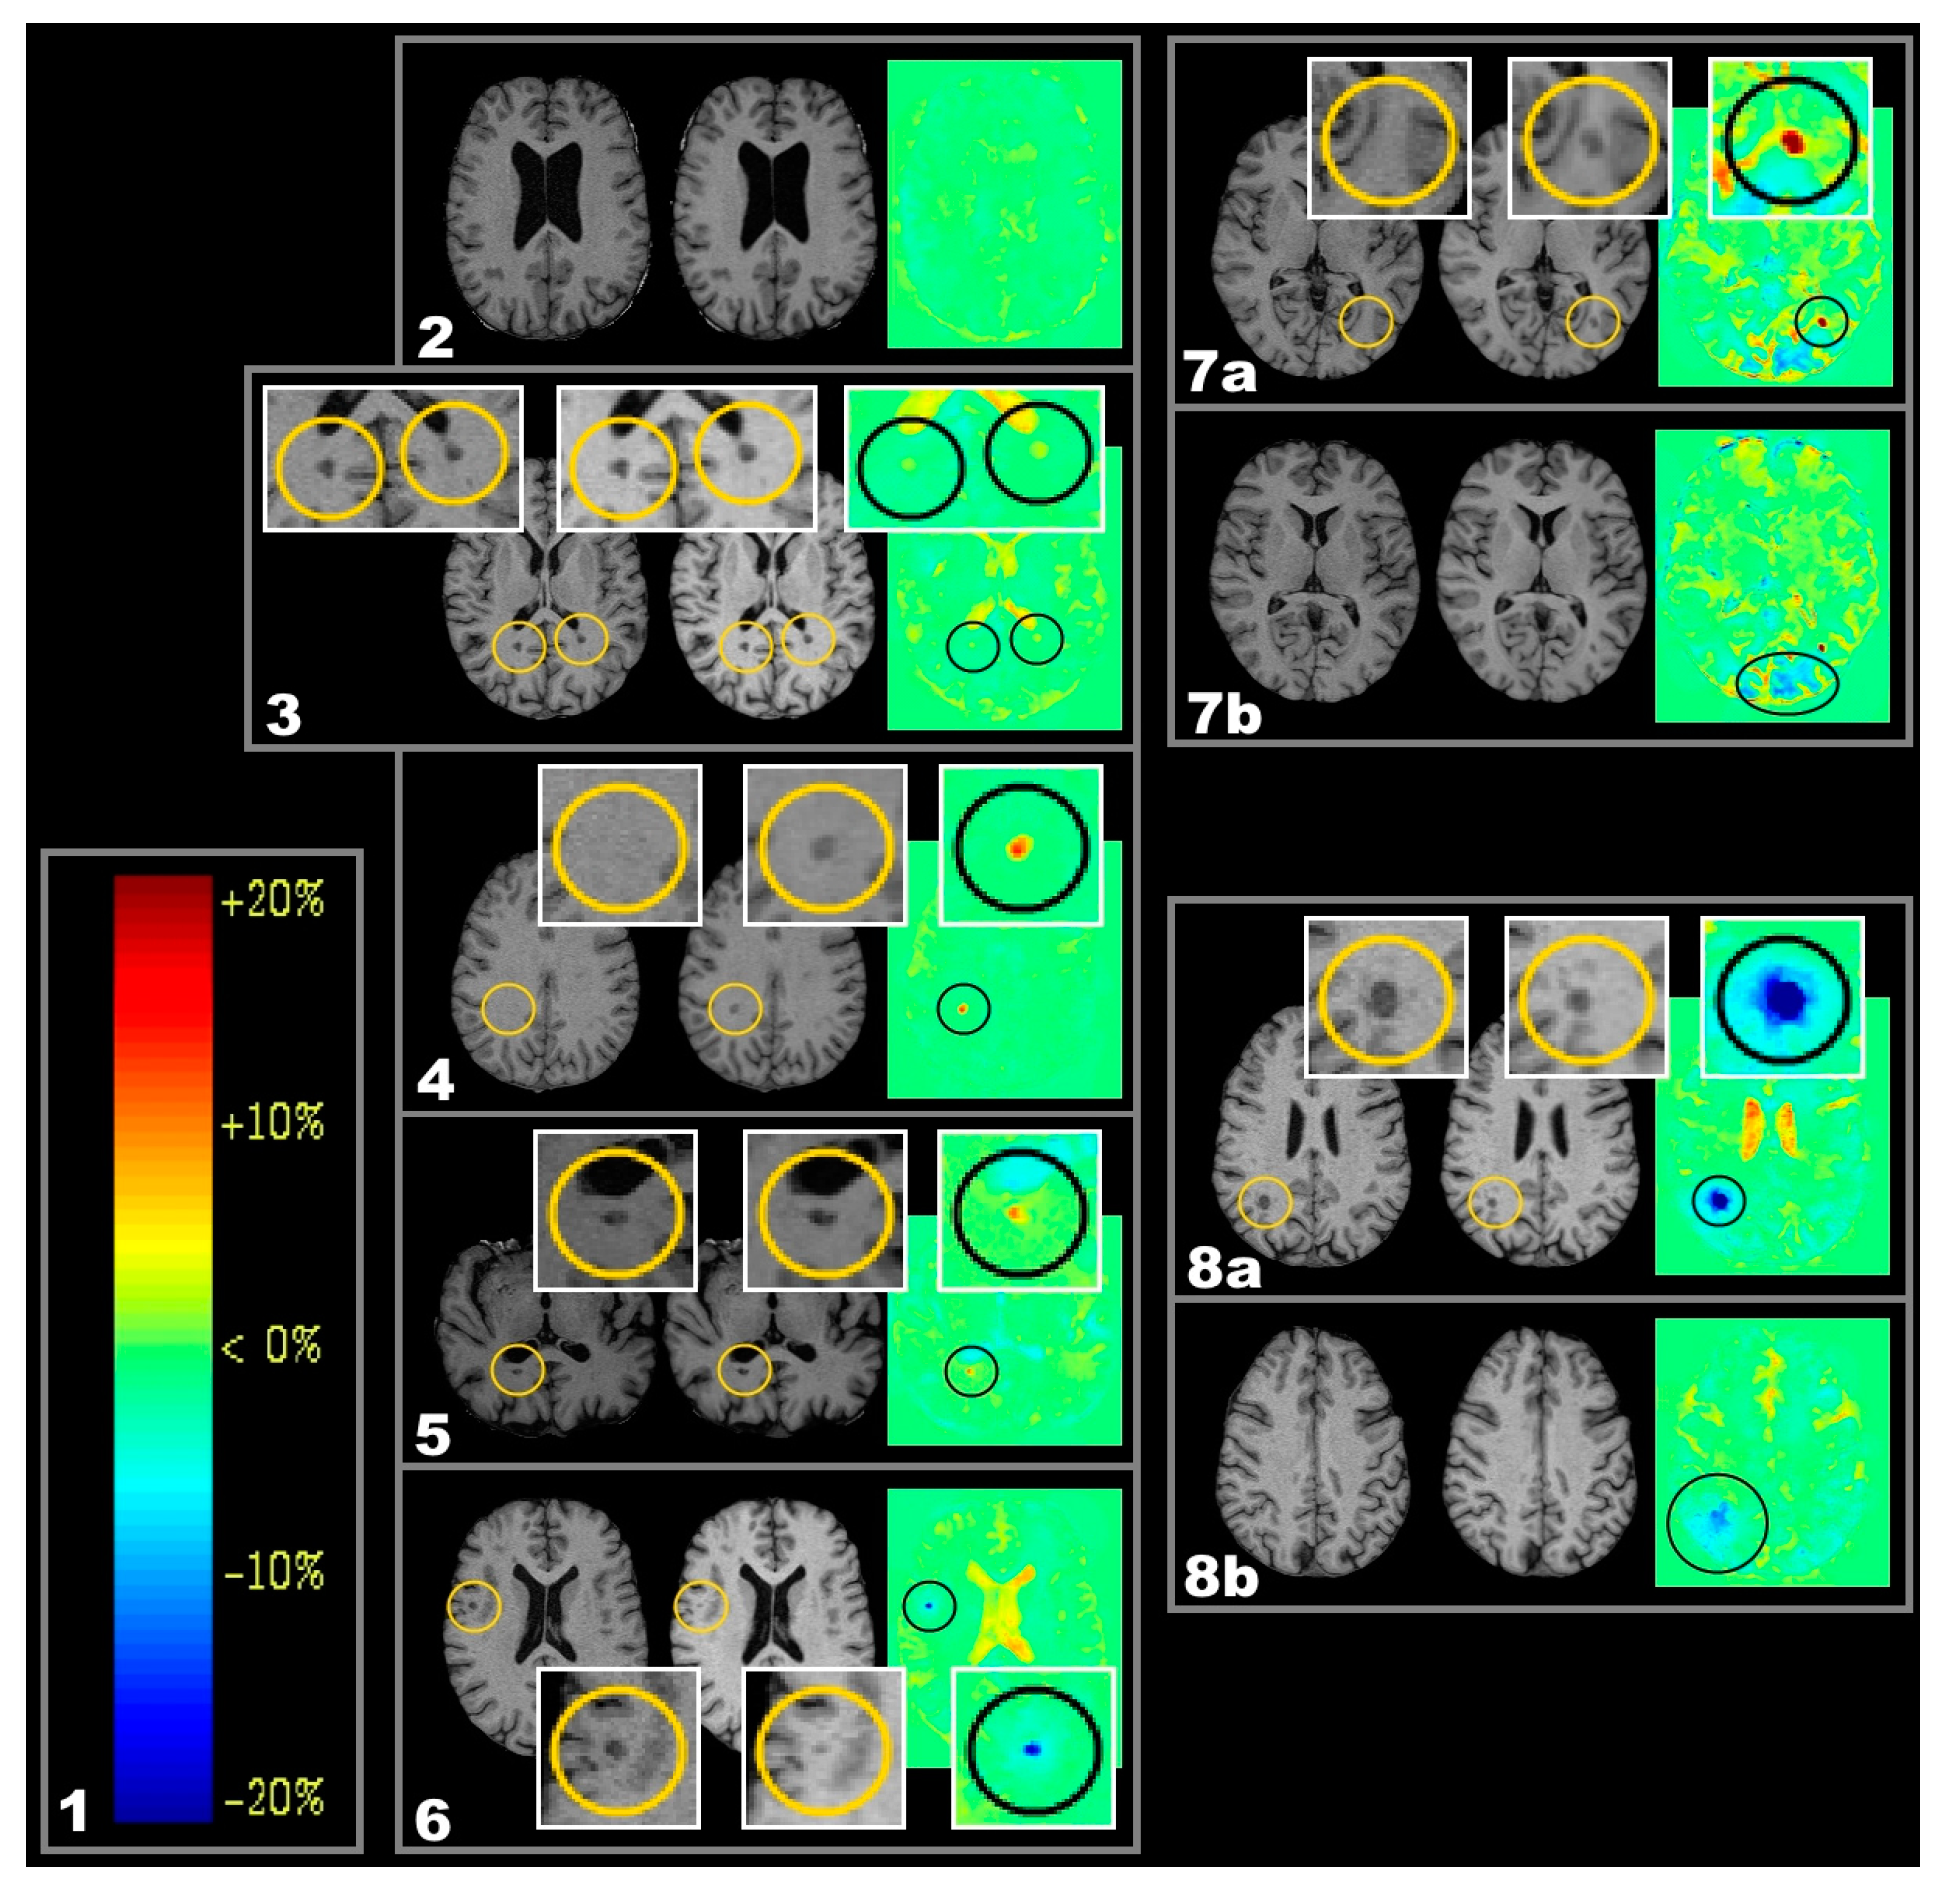

2.1. Lesion Types

3.1.1. Chronic Shrinking Lesions